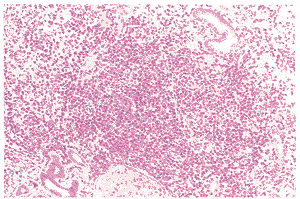

病理檢查可見肺泡結構消失,其內有邊界不清的肉芽腫,血管炎以血管為中心和侵入血管的細胞浸潤性損害為主,浸潤細胞有正常淋巴細胞、漿細胞、組織細胞、異形淋巴細胞樣及漿細胞樣細胞、網狀內皮細胞,異形細胞的形態呈有絲分裂,與淋巴增生性疾病相同,偶見大的淋巴細胞。部分小血管可因淋巴細胞浸潤後阻塞而引起肺局部栓塞和壞死,但此類情況很少見。

肺良性淋巴細胞血管炎和肉芽腫病BLAG的確診有賴於肺活檢,病理檢查可見肺泡結構消失,其內有邊界不清的肉芽腫,血管炎以血管為中心和侵入血管的細胞浸潤性損害為主,浸潤細胞有正常淋巴細胞、漿細胞、組織細胞、異形淋巴細胞樣及漿細胞樣細胞、網狀內皮細胞,異形細胞的形態呈有絲分裂,與淋巴增生性疾病相同,偶見大的淋巴細胞。部分小血管可因淋巴細胞浸潤後阻塞而引起肺局部栓塞和壞死,但此類情況很少見。本病需要與淋巴瘤樣肉芽腫、Wegener肉芽腫病等相鑑別,缺乏壞死改變是本病與Wegener肉芽腫的主要鑑別點。